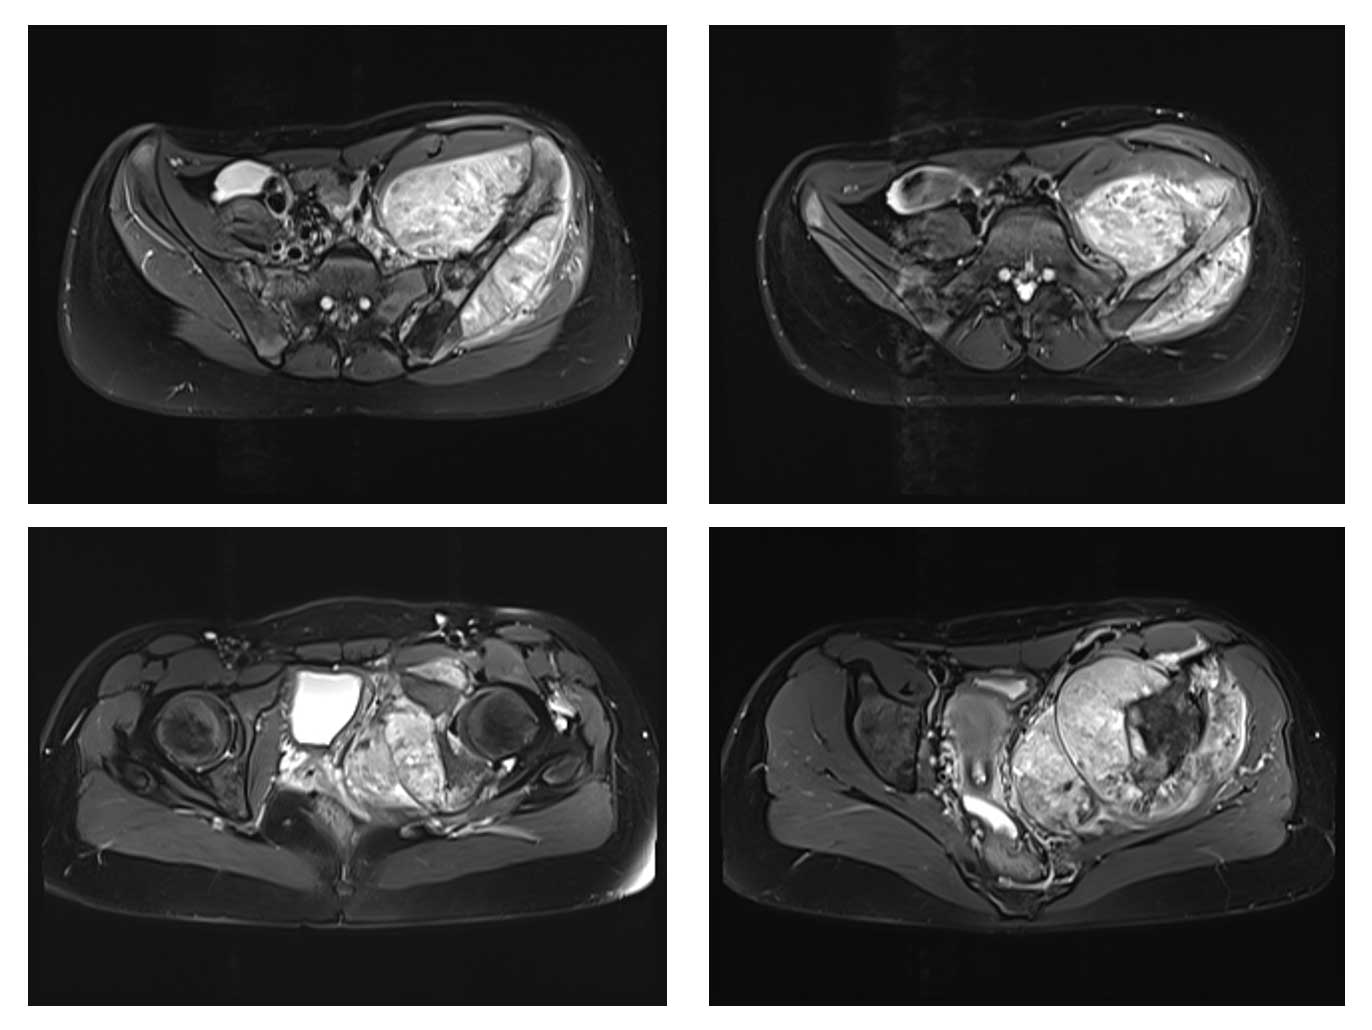

Ameliyat Öncesi: MR’da lomber 5. vertebra, sakrum ve iliak kanatın tamamını tutan kemikte harabiyete neden olup yumuşak dokuya uzanan büyük tümör dokusu görülmekte.